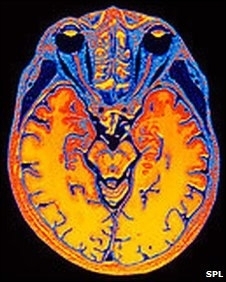

Pesquisadores de uma universidade britânica disseram ter conseguido diferenciar as memórias de pessoas por meio da análise de exames cerebrais.

Os cientistas então pediram aos voluntários que se lembrassem dos filmes, um de cada vez, ao mesmo tempo em que era realizado um exame de ressonância magnética para verificar a atividade cerebral. Este exame foi então estudado com um programa de computador.

Em exames de ressonância posteriores, por meio da verificação do padrão de atividade cerebral, os cientistas foram capazes de identificar em qual dos filmes os voluntários estavam pensando.